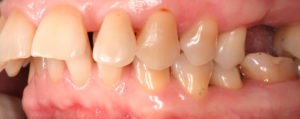

Искривление окклюзионной кривой (плоскости смыкания зубов), возникшее в результате парадонтита, успешно удалось устранить, используя накусочные брекеты на верхних резцах и микроимплант, установленный во фронтальном участке нижней челюсти: